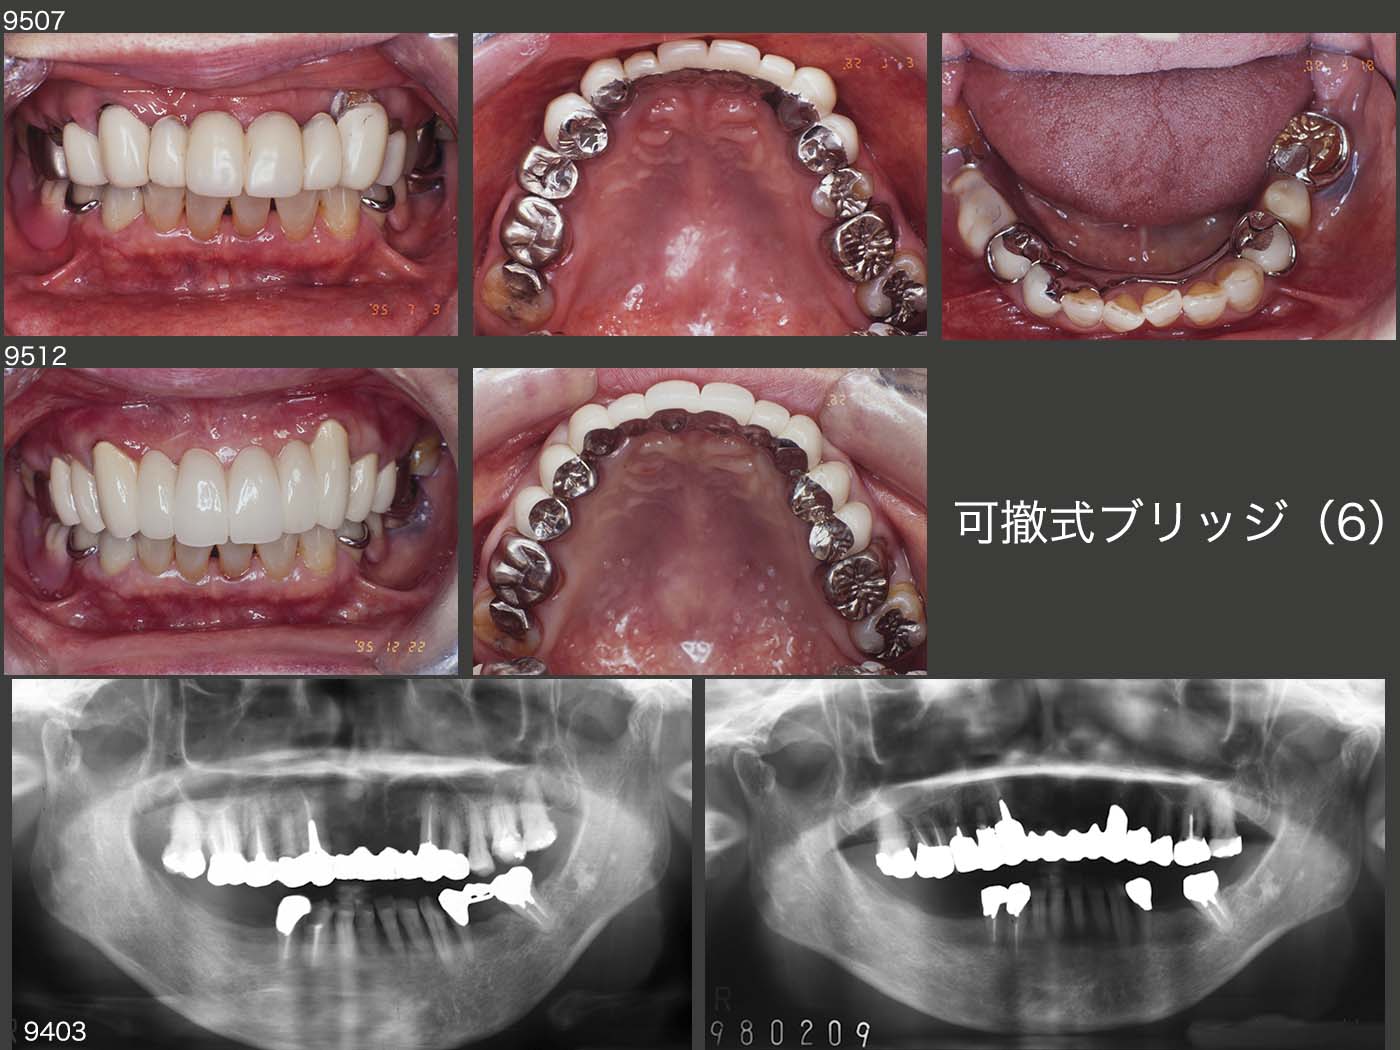

私が歯科医師になって2年目に治療した患者さん.1981年に右下ブリッジを自分で技工を行い,装着した.いわゆるロング・スパン・ブリッジである.暫くお目にかからなかったが,私が歯科医院を開業したのを機に,14年振りに95年11月に来院した.(中段パノラマX線写真)

2005年に左下7を歯根破折で失ったが,義歯を装着しないまま経過した.スライド下段は10年10月の状態.

2011年8月,歯根破折が原因で左上4を抜去し,12年2月に③4⑤のブリッジを装着した.ここで,左側大臼歯部でも咀嚼してもらいたいため,12年10月,左下にコーヌス義歯を装着した.(スライド上段)

この患者さんの習慣性咀嚼側は左側と思われる.だからこそ右下のロング・スパン・ブリッジが30年以上保ったといえる.さらに,ブリッジのポンティックを極端に小さくしたことが,左側咬みを助長したと思われる.13年7月,右下ブリッジのマージン部にう蝕がみられたのを機に,作り直しに同意していただいた.14年,右下に,可撤式ブリッジ(コーヌス義歯)を装着した.